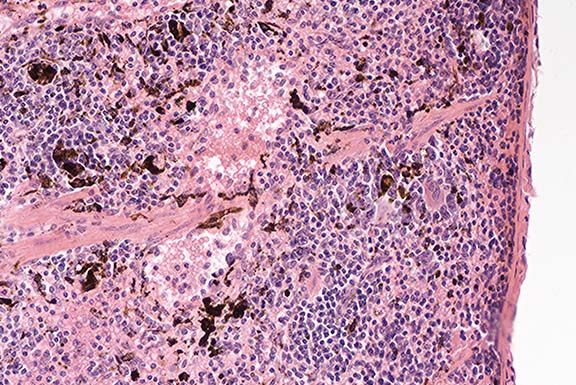

Signalment: A 2-month-old normal female laboratory mouse is submitted. The background is B10.A(2R)/SgSnJ.

History: The mouse is normal and submitted to illustrate a strain specific feature.

Gross Pathology: The cranial portion of the spleen has a discreet black focus present.

Conference Note: Hemosiderin and melanin can look similar in histologic sections of spleen, and can be present simultaneously. Melanin-containing cells in the spleen sometimes have a "stringy" appearance due to the presence of one or more dendritic processes. The gross observation that all or part of a tissue is black is a helpful diagnostic aid.

In this case, the Perls iron stain was negative and the Fontana-Masson method for melanin was positive.